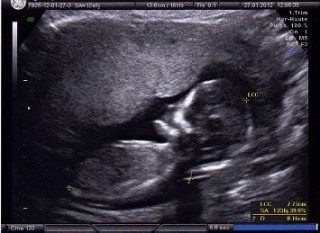

三人目の妊娠。長男次男→次は…(^0^;)!!まだはっきりとは教えてくれませんでした(笑)

何かついているように私には見えました!!

体の大きさは順調!足は長めとのことでした!(^^)!

手足をパタパタ動かしてました(*^^*)

背中を向けていました!

そろそろ性別分かるかな??

心拍も元気よく

ぐるぐる動き回ってました♪

CRL:約8cmほど(14w4d程)